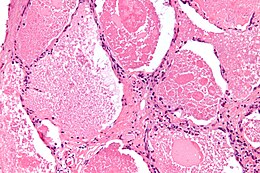

Description de l'image Pulmonary alveolar proteinosis -3- high mag.jpg.

La protéinose alvéolaire pulmonaire est une maladie rare consistant en l'accumulation de lipoprotéines dans les alvéole pulmonaires.